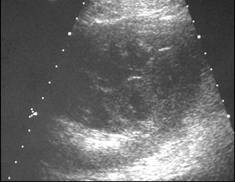

Subcapsular collection